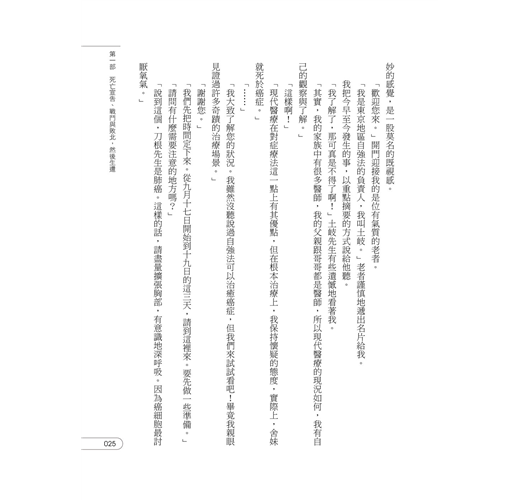

我的癌細胞在短短二十天內消失了

2016年9月1日確診罹患肺腺癌(四期),隔年6月發現癌細胞轉移腦部,當時醫師已經宣告「隨時可能停止呼吸」。後接受精密檢查發現,癌細胞甚至已轉移至兩眼、左右兩邊肺部、從肺部至頸部的淋巴、肝臟、左右兩邊的腎臟、脾臟、全身骨頭,然而,在絕望中卻出現神祕體驗。在經歷神祕體驗,住院一個月後,奇蹟般地完全康復。至2017年7月底回醫院檢查後,發現體內癌細胞完全消失。現在,在日本各地演講,分享自己從癌末生還的體驗中學習到與察覺到的事物,也將體驗與心情書寫出來分享大眾。